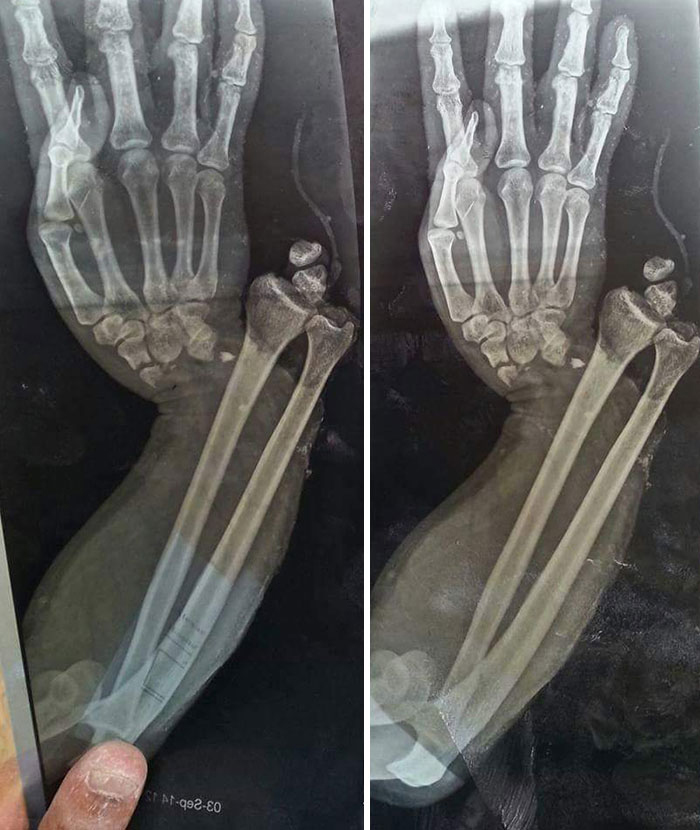

My (Nearly 60-Years-Old) Father's Arm After Being Thwomped By A Cow This Morning